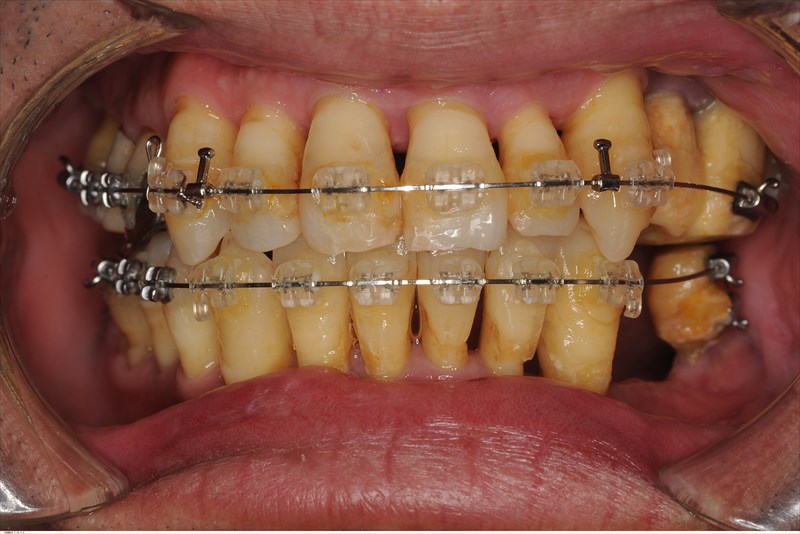

炎症のコントロールの後にこのように矯正治療を私が行い犬歯誘導ができるポジションまで歯の移動を弱い力で行います。